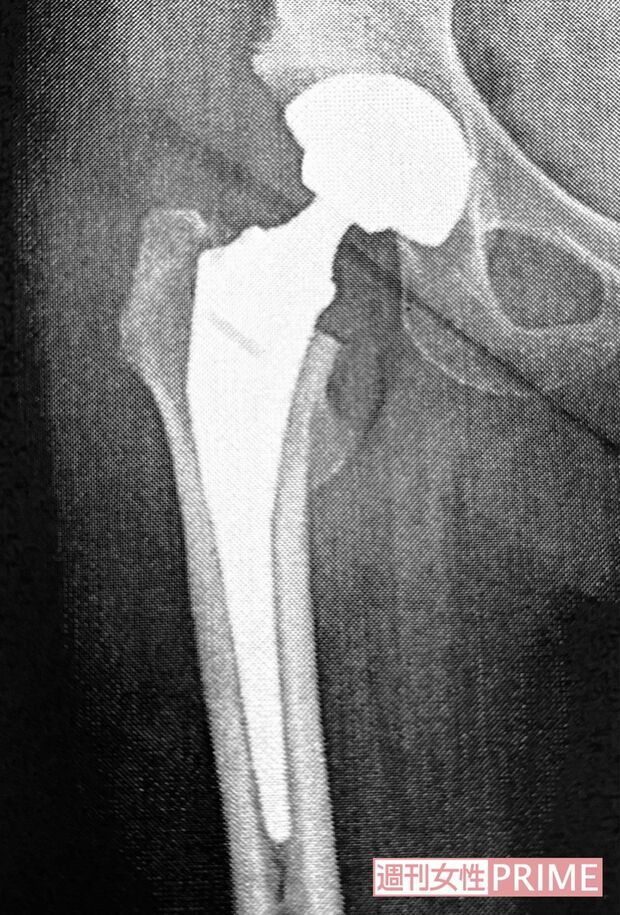

芸能 2025/6/1 ドラマ『おくさまは18歳』で一世を風靡した岡崎友紀さん、“人工股関節”に至った経緯と術中の様子を語る 女優テレビドラマ闘病 印刷 【写真】手術の翌日からリハビリを開始した岡崎さん 手術の翌日からリハビリを開始した岡崎友紀さん。股関節の可動域ゼロ状態から、どんどん脚が動くようになるので楽しかったとか 岡崎友紀さんの右脚に入っている人工股関節のエックス線画像 人生初の入院が人工股関節置換術だった岡崎友紀さん。「病院の提出書類が多いのにびっくり。署名するのが大変でした」 岡崎友紀さん 岡崎友紀さん 広告を見ると、続きの写真を見ることが可能になります 続きの写真を見る ページをリロードする 記事詳細を見る facebook いいね X ポスト LINE はてなブックマークに追加 女優の記事一覧を見る タレコミを投稿する 今日の運勢を無料で見る コピーしました